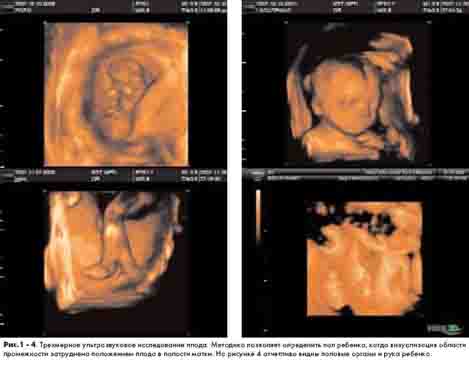

Новый метод уже достаточно широко используется в акушерской практике, позволяя улучшить диагностику различных аномалий развития, а также оказывая положительное психоэмоциональное воздействие на родителей, для которых изображение их будущего ребенка стало вполне реальным и понятным (см. рис. 1-4). Следует отметить, что до восьмой недели беременности трехмерное ультразвуковое исследование малоинформативно. С 10-й по 16-ю неделю можно увидеть плод целиком, его позу, руки, ноги, пуповину (без отчетливых мелких деталей). Оптимальные сроки беременности для трехмерного УЗИ - от 15 до 30 недель. В этот период нередко удается даже увидеть мимику плода.